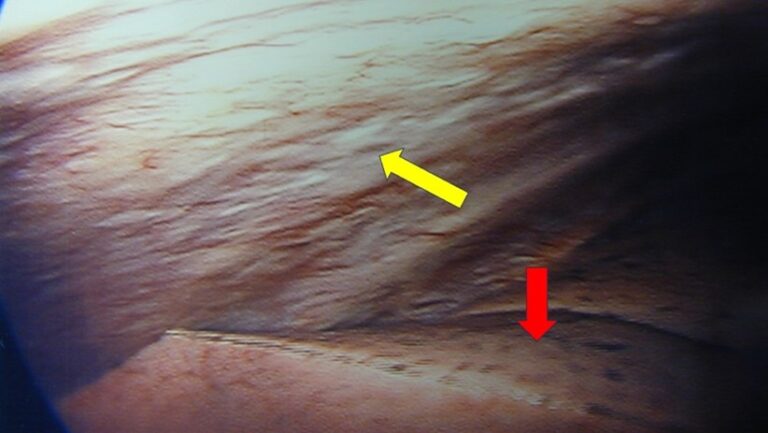

Αυτή είναι μια φωτογραφία μετά τοποθέτηση ενός τηλεσκοπίου μέσα στο θώρακα. Βλέπουμε το εσωτερικό του θώρακα και στο κάτω μέρος τον πνεύμονα με το κόκκινο βέλος, ενώ το κίτρινο βέλος μας δείχνει την περιοχή όλη που καλύπτει ο υπεζωκότας.

Στις επόμενες φωτογραφίες βλέπουμε το θώρακα ενός νέου ασθενή γεμάτο με ρυπαρό υγρό λόγω βαριάς πνευμονίας.

Στην επόμενη φωτογραφία και μετά τον πλήρη καθαρισμό το πύον έχει πλυθεί και ο πνεύμονας έχει αρχίσει να εκπτύσσεται και πάλι.